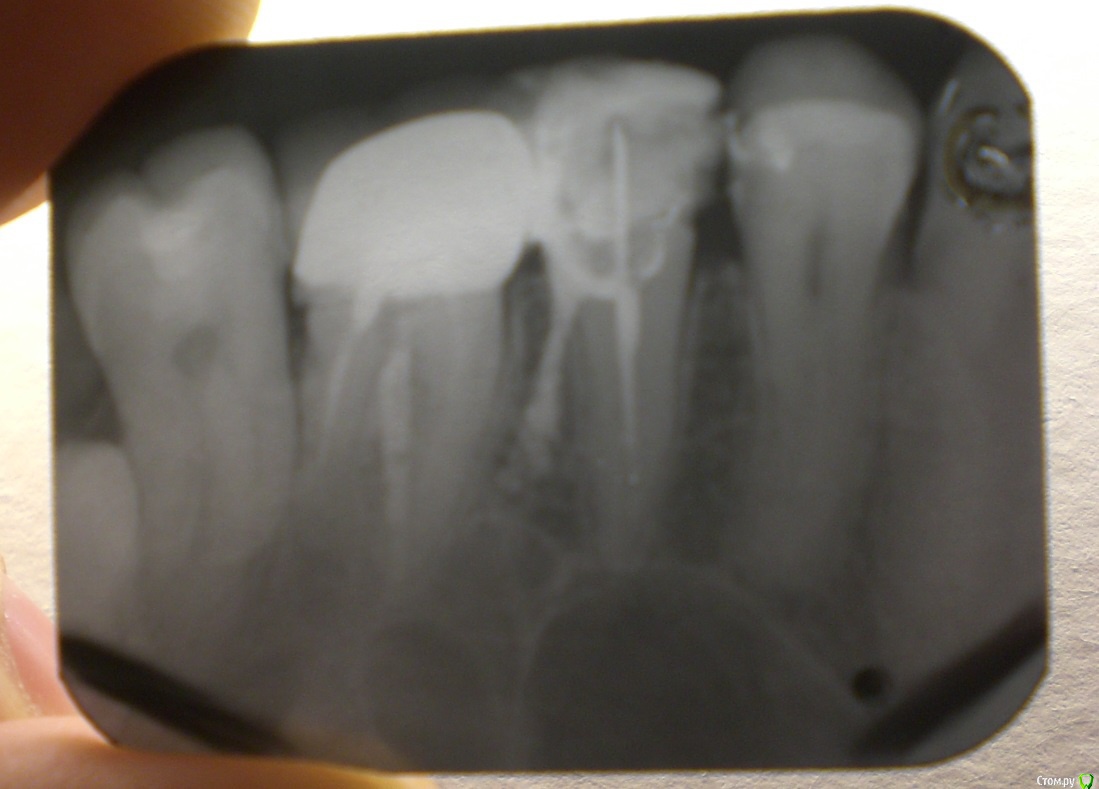

Эдвард Опубликовано 6 января, 2015 Поделиться Опубликовано 6 января, 2015 ЗдравствуйтеПосоветуйте пожалуйста , что мне теперь делать с такой пломбировкой? Ссылка на комментарий

Kolchanov Опубликовано 6 января, 2015 Поделиться Опубликовано 6 января, 2015 Смотря что за материал. Скорее всего частично организм переварит. Не очень хорошо то, что у зуба дыра лишняя, через которую материал выведен. По такому снимку нельзя сказать, куда его вывели, под десну, в костную ткань...Меняйте доктора, короче. Надо вживую смотреть. Вполне возможно, что есть смысл растаться с зубом уже сейчас. Много моментов. 1 Ссылка на комментарий